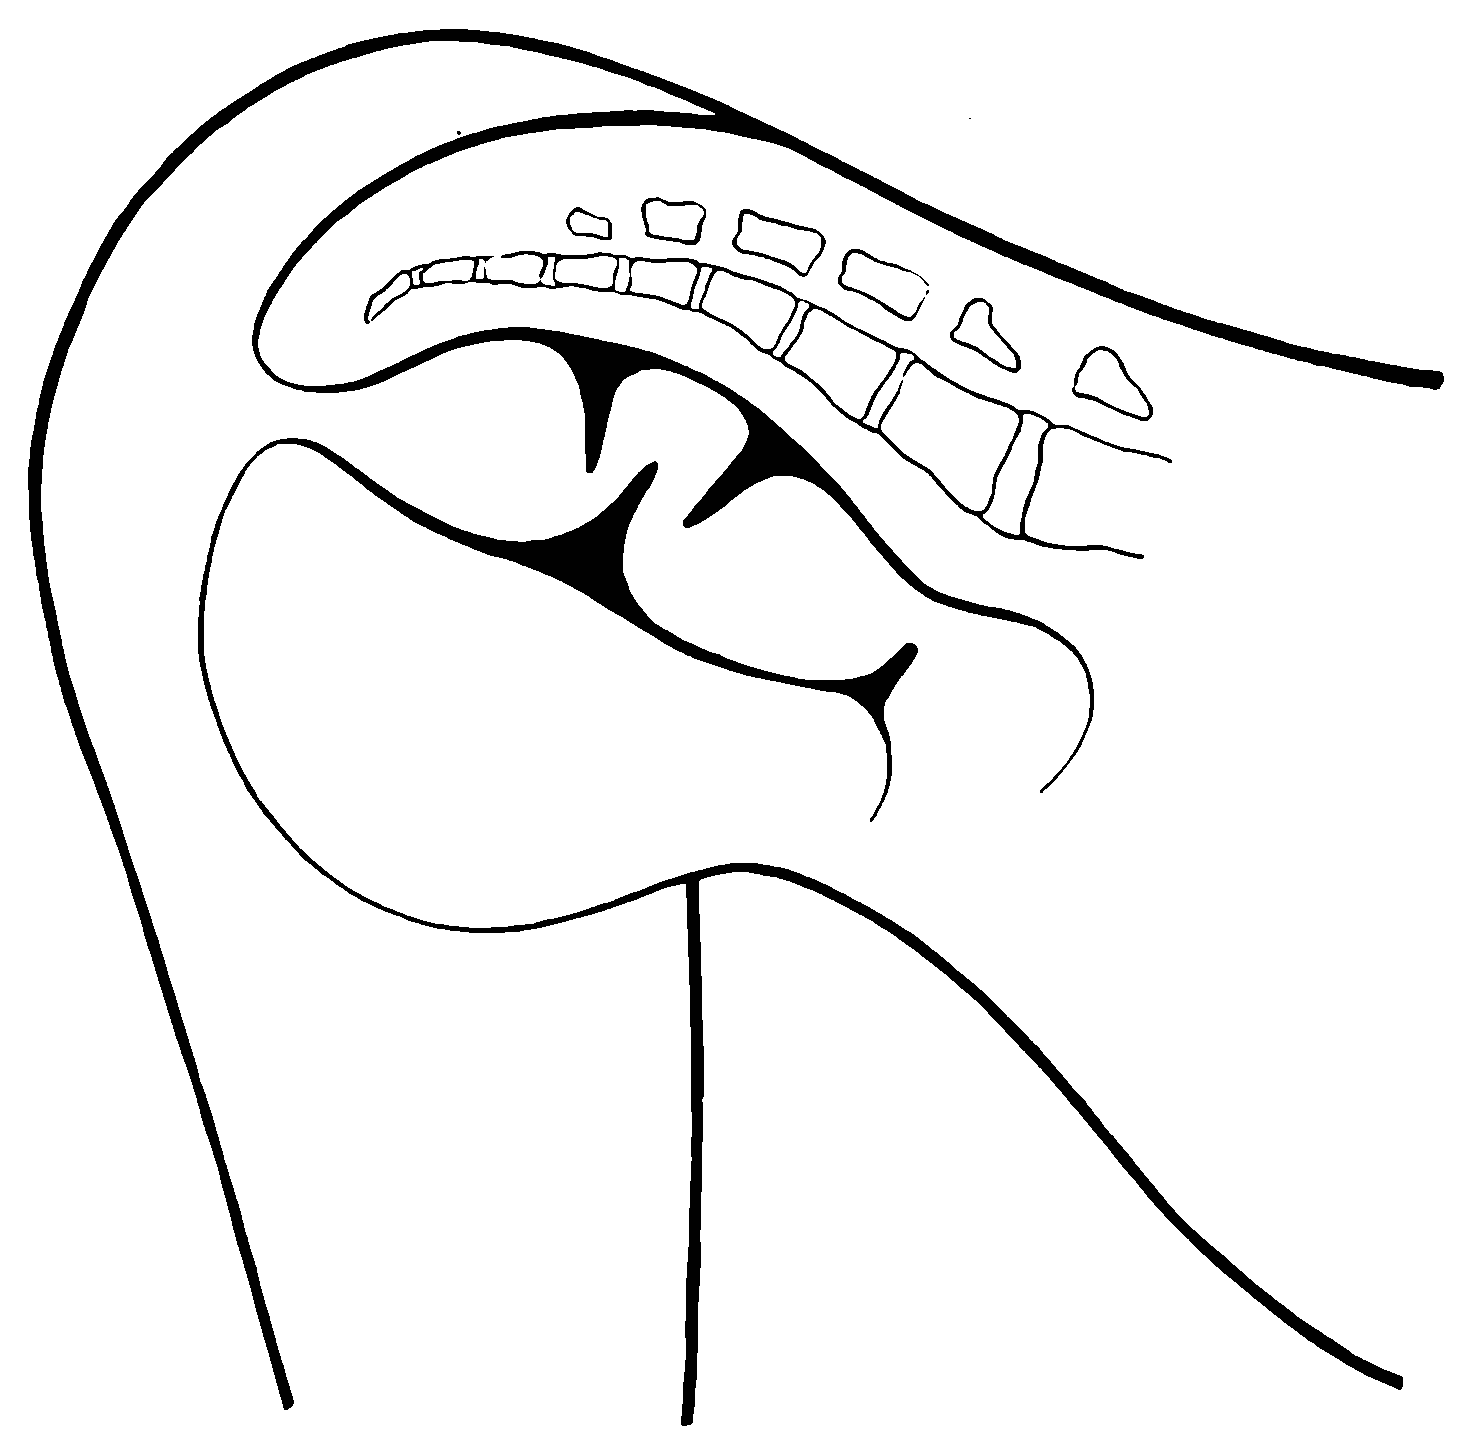

Fig. 19.—Drawing of specimen No. 281 in the Anatomical Museum of the Royal College of Surgeons, London. The dissection was made by Mr. William Pearson. The drawing shows in the lower part of the field the coccyx, in the upper part of the field the pubes.

Fig. 20.—Drawing of specimen No. 284 in the Anatomical Museum of the Royal College of Surgeons, London. The dissection was made by Mr. William Pearson. The drawing shows in the lower part of the field behind the rectum the coccyx, in the upper part of the field the pubes.

The fixed anal rectum begins at the levator ani and coccygeus muscles. The levator ani has its origin at the sides of the bodies of the pubic bones, the coccygeus at the spines of the ischii, and the levator ani has additional origin from the fascia and bony parts on a line between these two points. The fibers of these muscles are directed downward and inward to the fixed anal rectum; many fibers are blended into the contiguous structures of the pelvic floor. The coccygeolevator muscles may be compared to an opened slat-fan, the apex having its place at the anus, and its long border representing the line of origin of the muscles, Fig. 19. The ental sphincter ani muscle, situated a few lines below the levator ani, is made up of an aggregation of the fibers of the circular non-striated muscular intestinal coat, Fig. 20. The ectal sphincter ani striated muscle is situated immediately beneath the external skin. It serves the present occasion to describe the ectal sphincter of the male as a loop of muscle thrown about the terminal end of the rectum and hitched to the terminal bone of the coccyx, and in the female as a longer loop of muscle twisted upon itself so as to make a tandem-loop,[56] which, in the form of the figure eight (8), is thrown about the vagina and terminal end of the rectum.